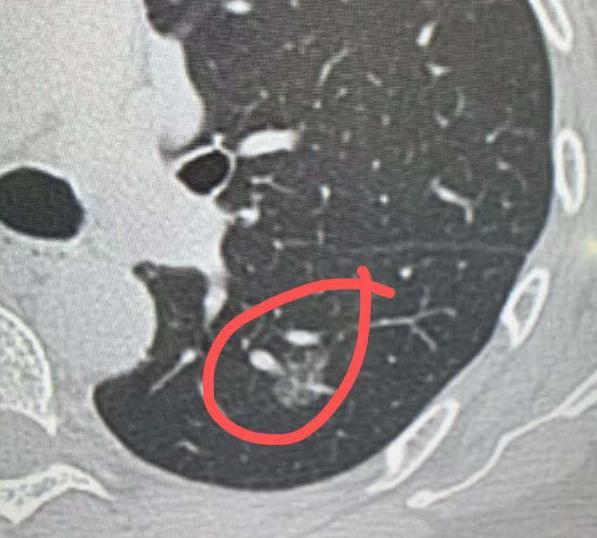

4mm磨玻璃结节,术后确诊肺微浸润癌?不少朋友查出几毫米的肺磨玻璃结节,还听说可

奇怪的事很多,肺部结节切出来确诊是肺癌,在体内已经开始腐坏!看病人多了,什么病